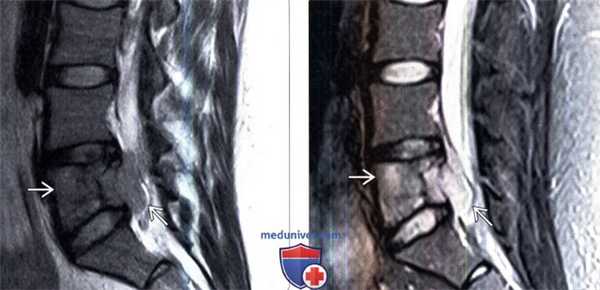

(Слева) На схеме показано замещение тела позвонка саркомой Юинга, являющееся причиной умеренного коллапса позвонка. Опухоль через небольшие перфорации в кортикальных пластинках распространяется в окружающие мягкие ткани.

(Справа) На аксиальном КТ-срезе с КУ определяется массивная опухоль Юинга паравертебральных мягких тканей, распространяющаяся в левую поясничную мышцу, дорзальные паравертебральные мышцы, вызывающая деструкцию левой половины тела поясничного позвонка и продолжающаяся эпидурально. (Слева) Аксиальный срез, Т2-ВИ: саркома Юинга, поражающая паравертебральные мышцы и распространяющаяся эпидурально, сдавливая и оттесняя дуральный мешок вправо. Инфильтрация опухолью тела позвонка в данном режиме видна плохо.

(Справа) Аксиальный срез, Т1-ВИ с КУ: диффузно и неравномерно накапливающая контраст опухоль, поражающая левую половину тела поясничного позвонка, эпидуральное пространство и паравертебральные и дорзальные мышцы.